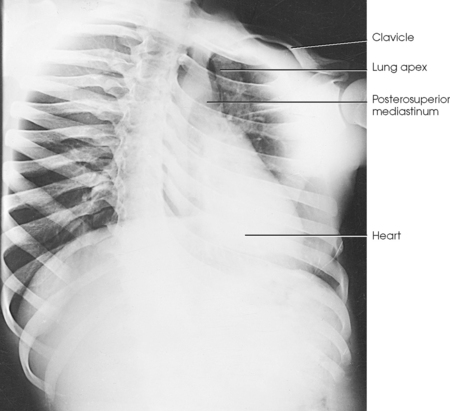

• Have the patient depress the shoulders and hold them in contact with the grid device to carry the clavicles below the lung apices. Except in the presence of an upper thoracic scoliosis, a faulty body position can be detected by the asymmetric appearance of the sternoclavicular joints. Compare the clavicular margins in Figs. 10-14 and 10-15.

Structures shown: The apices are projected above the shadows of the clavicles in the PA axial and PA projections (Fig. 10-58).